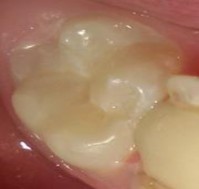

Răng Sau Khi Được Sơn Phủ Tạo Cửa Sổ Nghiên Cứu 3 × 3 Mm -

- Sơn một lớp chống axit trên mặt răng trừ lại một cửa sổ có kích thước 3× 3mm. chờ trong 10 phút để lớp sơn thứ nhất khô tiếp tục sơn thêm lớp thứ hai.